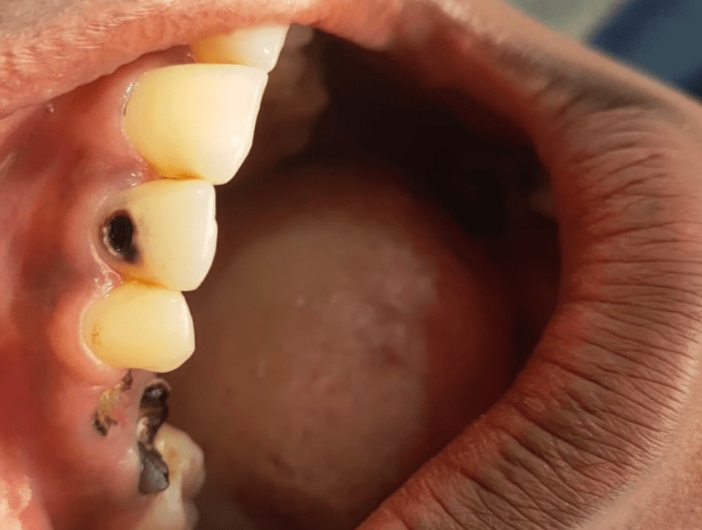

OUR TEETH REMOVAL RESULTS

The seamless outcomes of our gentle, professional tooth removal procedures.

Before Extraction